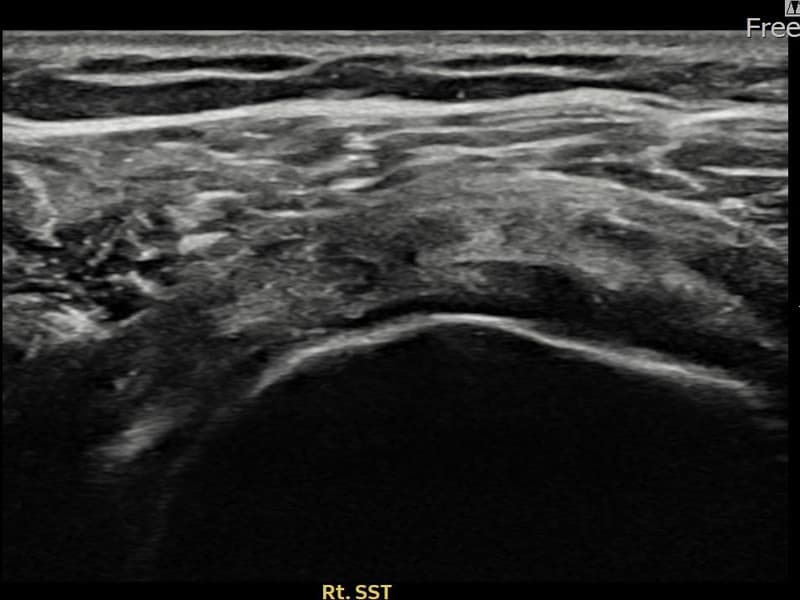

术后

术前超声确认右侧 冈上肌腱 关节面侧撕裂进展型,右侧冈上肌腱回声不连续伴肌腱缺损(12mm × 7mm (肌腱厚度约55%缺损))。术后超声显示撕裂部位充满再生组织,肌腱连续性恢复,回声模式正常化。